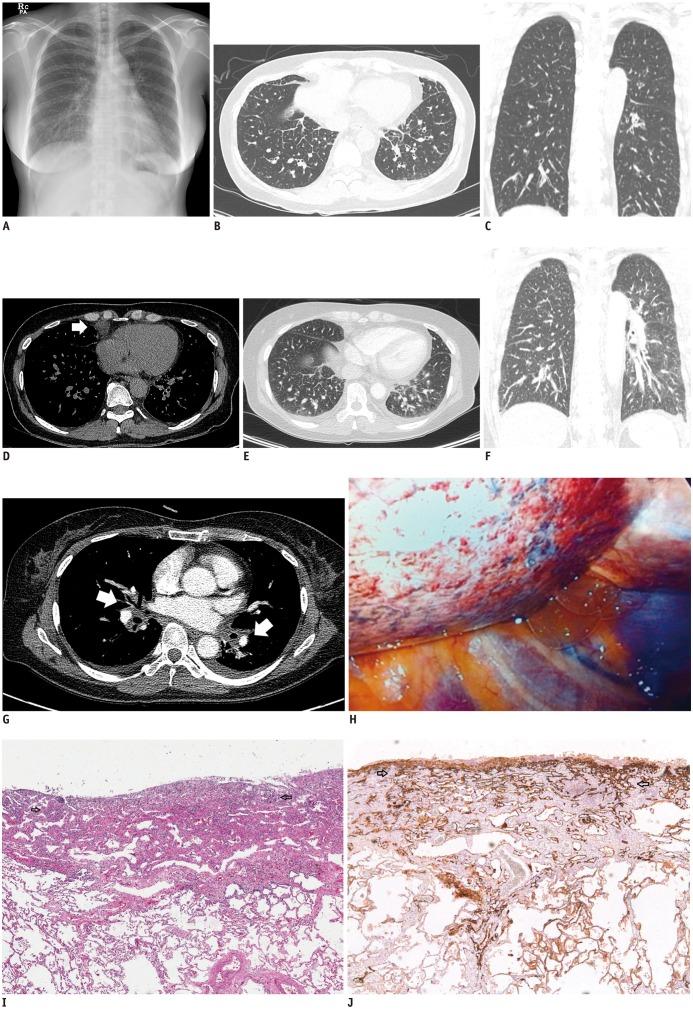

Diffuse pulmonary lymphangiomatosis (DPL) is a rare lymphatic disorder characterized by lymphatic channel proliferation. It is mostly reported in children and young adults. Here, we report a case involving a 52-year-old asymptomatic woman who presented with increased interstitial markings, as seen on a chest radiograph. Diffuse interstitial septal thickening was found on a serial follow-up chest computed tomography scan, and lymphangitic metastasis was the primary radiologic differential diagnosis. However, histologic sections of wedge resected lung revealed diffuse pleural and interlobular septal lymphatic proliferation characteristic of DPL.

弥漫性肺淋巴管瘤病(DPL)是一种罕见的淋巴系统疾病,其特征为淋巴管增生。它主要发生在儿童和青年。在此,我们报告一例 52 岁无症状女性患者,其胸部 X 线片显示间质性纹理增多。连续随访的胸部 CT 扫描发现弥漫性间质间隔增厚,淋巴管转移是主要的影像学鉴别诊断。然而,楔形切除肺组织的组织学切片显示弥漫性胸膜和小叶间隔淋巴管增生,符合 DPL 的特征。